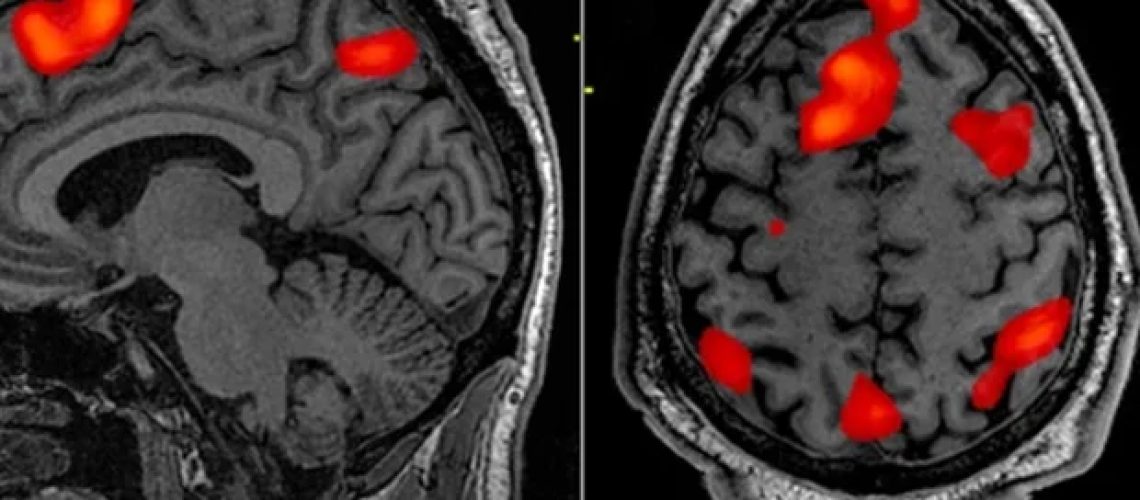

מחקר חדש בקרב מגיבים של מרכז הסחר העולמי (WTC) עם הפרעת דחק כרונית פוסט-טראומטית (PTSD) חשף שינויים פיזיים הניתנים למדידה במבנה המוח שלהם, התואמים את השינויים באיזון של נוירונים ממיאלין ללא מיאלין (תאי עצב המוליכים מהירים ואיטיים) על פני שתי ההמיספרות של המוח. שינויים אלו היו קשורים באופן החזק ביותר עם חוויה חוזרת של סימפטומים אצל אנשים עם PTSD. ההבדלים בקליפת המוח שנמצאו במחקר הדמיה מתוחכם זה ב פסיכיאטריה ביולוגית: מדעי המוח הקוגניטיביים והדמיהשפורסם על ידי Elsevier, עשוי לשמש כסמנים ביולוגיים תחליף לבריאות המוח הנפגעת אצל אנשים הסובלים מ-PTSD כרוני, כמו גם פוטנציאל להודיע ​​על אסטרטגיות סקר מוקדם.

מחקר זה השתמש בהדמיה עצבית של ניגוד אפור-לבן (GWC), טכניקה מבוססת MRI שנועדה לשפר מחקרים על בריאות עצבית עבור אנשים שעברו טראומה. GWC פועל כפרוקסי לצפיפות מיאלינציה תוך קורטיקלית, בוחן את הטשטוש הנראה בממשק החומר הלבן והחומר האפור בהתבסס על הבדלים בעוצמת האות. עלייה בניגוד מייצגת גבול חד יותר, המעיד על מעבר בריא מחומר אפור לחומר לבן מוחי. גבול פחות מובהק (GWC נמוך) מצביע על ריכוז לא תקין של מיאלין (שכבת בידוד שומנית), המצביע על הפרעה במהירות העיבוד והעקביות של המוח.

בהערכת תמונות מוח מבניות עבור 99 מגיבים ל-WTC, חוקרים מצאו עדויות לשינויים נרחבים ב-GWC בחומר האפור בקליפת המוח על פני שתי ההמיספרות של המוח באנשים עם PTSD. הפחתות ב-GWC עשויות לרמוז שיש יותר תכולת מיאלין באזורים אלה מהרגיל במגיבים החשופים לטראומה ללא PTSD. הם גם מצאו שניתן לשלב את GWC עם סמנים אחרים לבריאות תוך קורטיקלית כדי לשפר את היכולת לעזור לזהות באופן אובייקטיבי מגיבים ל-WTC עם PTSD.